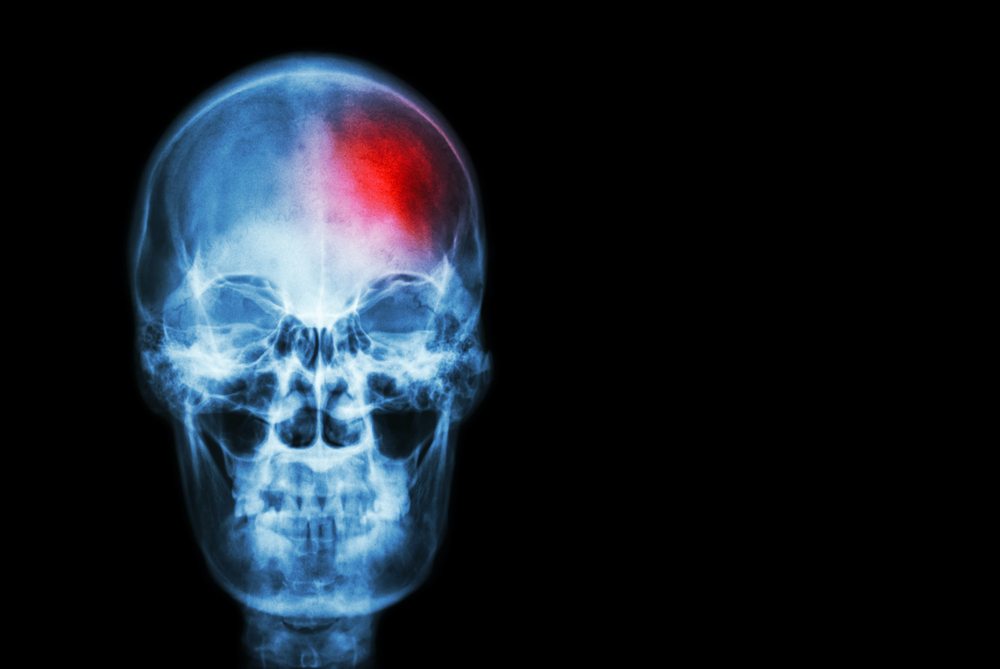

L’anosognosie est un symptôme qui apparaît fréquemment suite à un dommage cérébral comme la démence ou l’hémiplégie (paralysie d’un côté du corps due à un accident vasculaire cérébral), bien que l’on retrouve également ce symptôme lié aux troubles de la schizophrénie. C’est un problème biologique, du à un dommage cérébral, et n’est pas la même chose que la négation, qui est un mécanisme de défense psychologique que nous utilisons tous.

En observant les images neurologiques des cerveaux de personnes atteintes d’anosognosie on remarque qu’ils ont une activité plus faible dans certaines zones du cerveau que chez une personne qui a pleinement conscience de sa maladie.